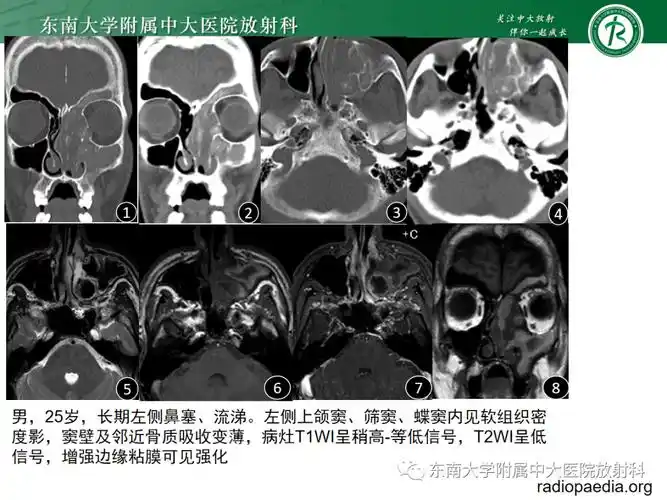

真菌性鼻窦炎